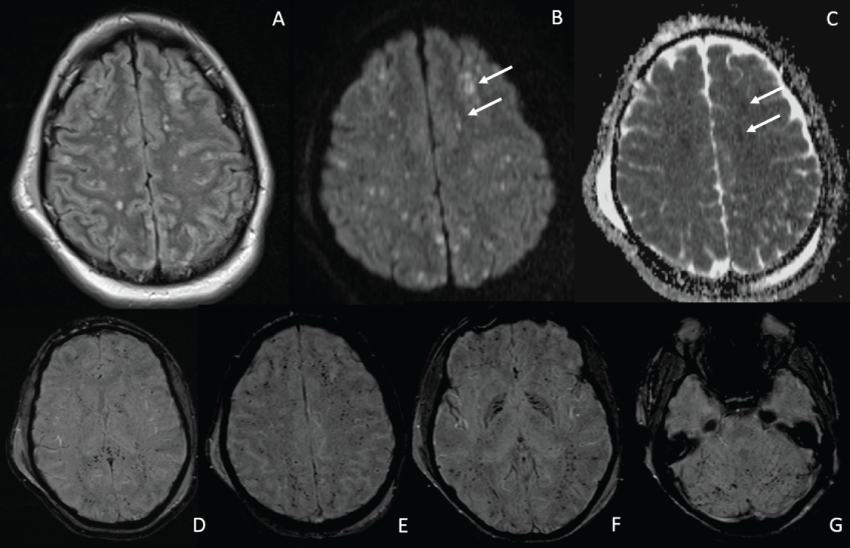

He required ventilator support for three days then was weaned rapidly to extubation. Due to a delayed return to normal sensorium, an MRI was performed which revealed abnormalities on fluid-attenuated inversion recovery (FLAIR), diffusion-weighted imaging (DWI), attenuation diffusion coefficient map (ADC), and susceptibility weighted imaging (SWI), as described in the caption for figure 3.

Figure 3: Scattered foci of hyperintensity are seen primarily within the deep white matter at the level of the centrum semiovale on the FLAIR image (Image A, arrows). While similar findings on FLAIR can be seen in older patients secondary to chronic white matter disease, the finding is unusual in this age group. There is corresponding high signal on DWI (Image B arrows), without associated high signal on the ADC map (Image C), consistent with foci of cytotoxicity secondary to microinfarcts rather than T2-shine through from vasogenic edema. The SWI image (image D) shows innumerable extensive fine foci of low signal intensity with a diffuse distribution.

Figure 5: High signal intensity foci of varying sizes are seen on FLAIR scattered throughout the convexities, and involving both superficial and deep white matter as well as cortex (image A). Many of these lesions have restricted diffusion and are cytotoxic rather than vasogenic, resulting in high signal on DWI (image B), and low signal on ADC (image C- arrows point to the same lesions on DWI and ADC map). The bottom four susceptibility weighted images (D-G), show low signal diffusely involving the corpus callosum (D), inter-digitate white matter and gray matter throughout the convexities (E), basal ganglia (F) and cerebellum (G). The relative lack of predilection for specific areas of the brain commonly involved in DAI (e.g. midline splenium of the corpus callosum, parahippocampal white matter, and dorsolateral brainstem or midbrain) and the extensive fine granular appearance of microhemorrhages on the SWI images is consistent with a radiologic diagnosis of CFES.

Both the above Gurd's Criteria and Schonfelds index focus on the general FES and have relatively limited weight for the neurologic aspects of the FES. To achieve a higher level of confidence when considering the diagnosis of CFES, MR imaging can be highly supportive and perhaps diagnostic. Non-gadolinium enhanced MRI of the brain, ideally performed with SWI and DWI is considered the imaging test of choice to confirm the specific diagnosis of CFES [15-18]. Specific lesions may present as scattered or confluent areas of hyper-intensity on fluid-attenuated inversion recovery (FLAIR) imaging. T2/FLAIR hyperintensities resulting from cytotoxicity may correspond with foci of restricted diffusion (high signal on DWI and low signal on ADC maps (Figure 2, Figure 5 and Figure 8), whereas areas of vasogenic edema, which may have an identical appearance on FLAIR, will be bright on both DWI and ADC- a phenomenon known as T2-shine through. Susceptibility-weighted images (SWI) may reveal foci of low signal intensity corresponding with diffuse petechial hemorrhages due to microvascular rupture again caused by severe vasculitis from FFAs. These petechial hemorrhages tend to be very small and much greater in number than the lesions seen in DAI.

DAI lesions tend to involve areas of the brain that impact against hard surfaces such as the falx and tentorium (especially the medial aspect of the genu of the corpus callosum, the septum pellucidum, and the posterolateral brainstem); that splay out as a result of impulsive forces during whiplash (the peri-frontal horn and parahippocampal white matter); or that demarcate transitions between parts of the brain with different densities and water content that are susceptible to shear stress (subcortical white matter along the convexities). On the other hand, CFES has a more diffuse distribution throughout the white matter, basal ganglia, and cerebellar hemispheres, and like other embolic phenomena, has a predilection for watershed areas. Unlike DAI, which typically spares the digitate white matter (just below the gyri) and the cortex, CFES involves both of these areas.

In CFES, hyper-intense lesions on FLAIR images are thought to be due to breakdown of the blood-brain barrier induced by severe vasculitis from free fatty acids (FFAs), resulting in vasogenic edema. Hyper-intense lesions on DWI that correspond with cytotoxic edema (i.e. those associated with low ADC values) are attributed to microvascular occlusion by fat droplets resulting in ischemic lesions. Diffusion tensor imaging measures fractional anisotropy. Water normally preferentially diffuses along axons, but when nerves become bloated as a result of histo-toxicity there is more radial diffusivity (RD). Greater proportions of radial diffusivity are associated with lower fractional anisotropy (FA), indicating nerve dysfunction is present. CFES is associated with higher radial diffusivity and therefore lower FA values than DAI.